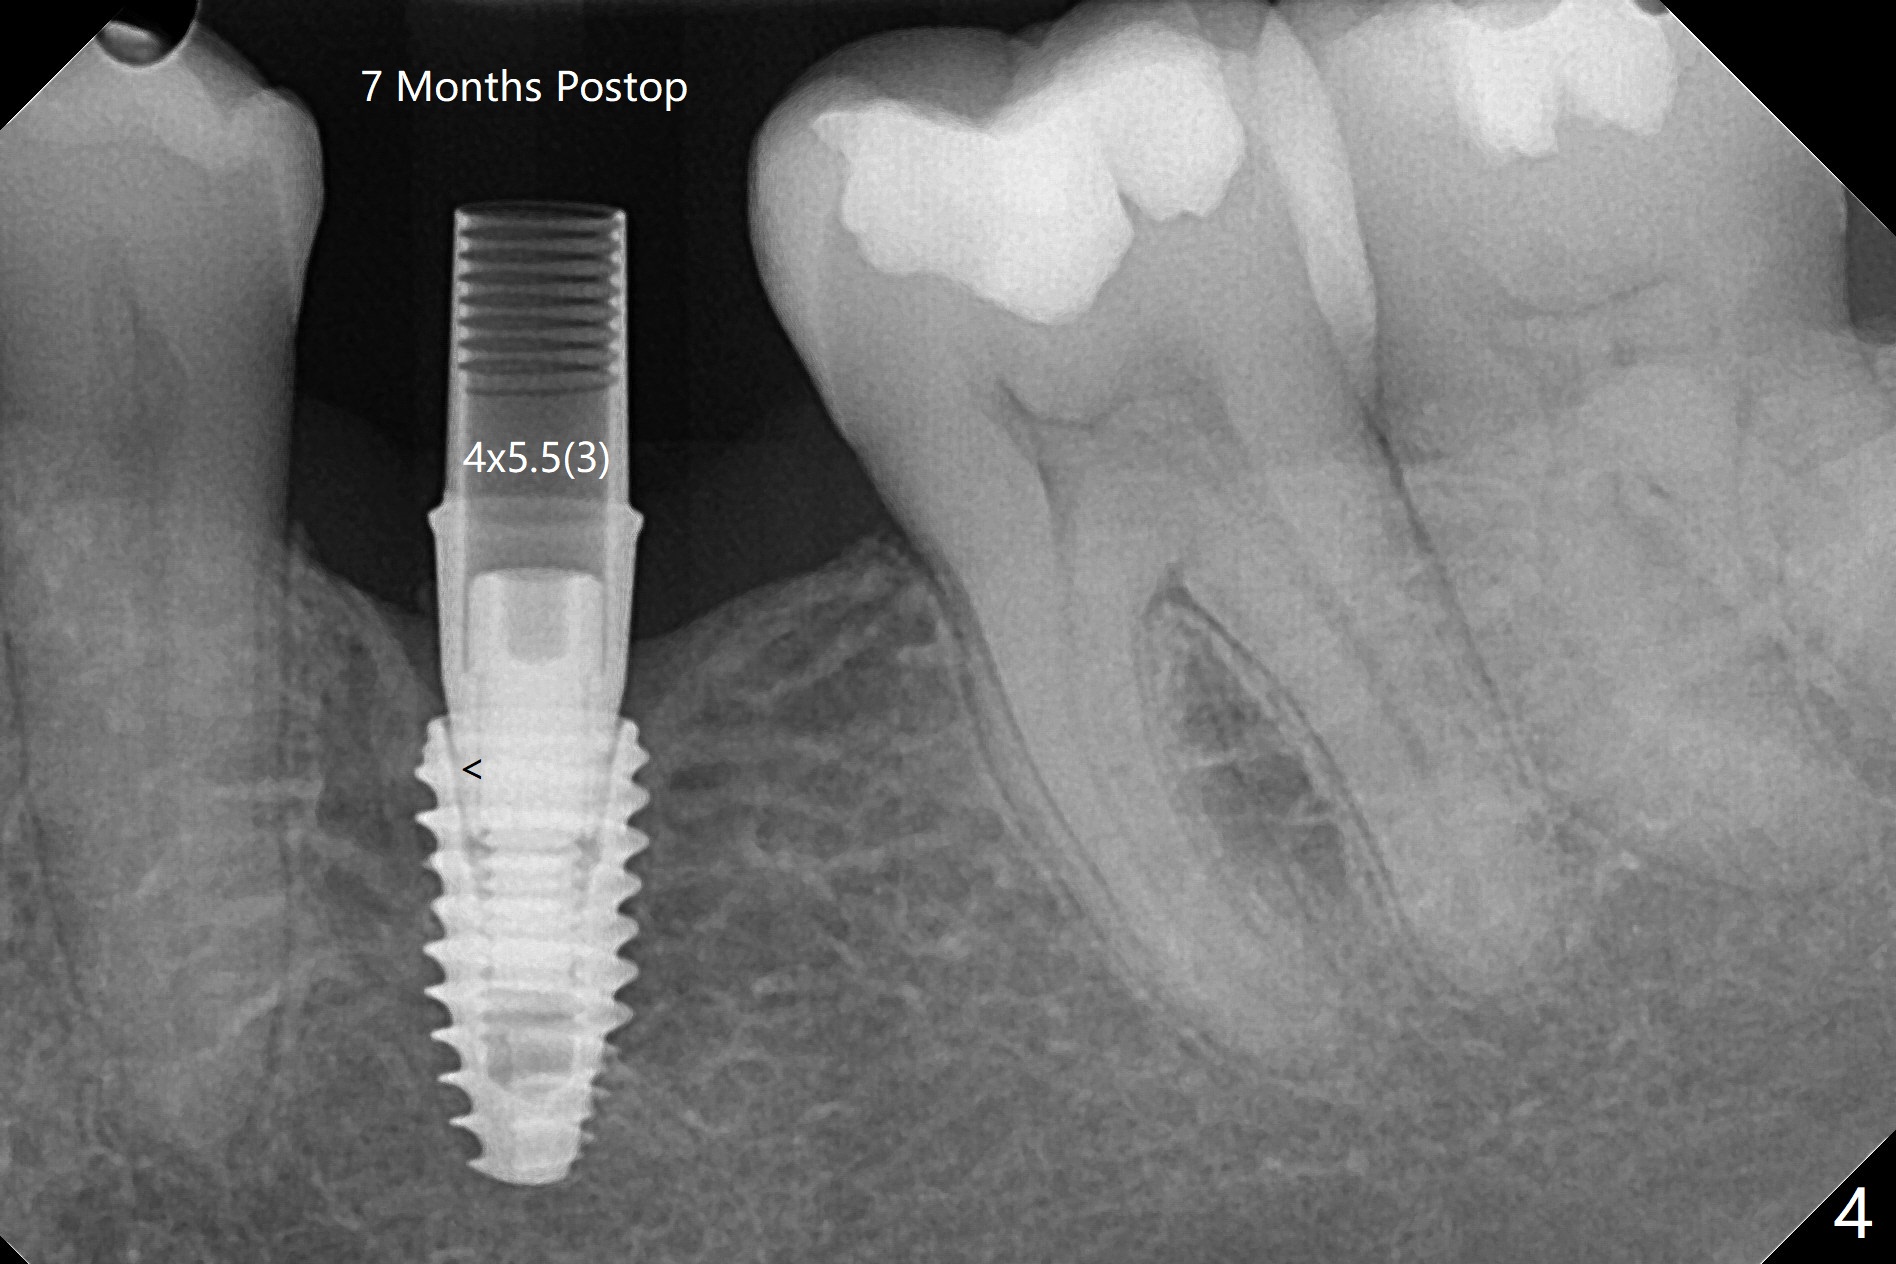

术后7个月左下4毫米修复基台无法就位(图四:箭头),局麻下使用4.6毫米Profile钻头后(去除软硬组织阻挡),4.5毫米修复基台顺利就位(图五)。右下第一次手术已经应用Profile钻头,牙槽嵴吸收,所以放置4.5毫米修复基台没问题(图六)。第一次手术应该使用Profile钻头。